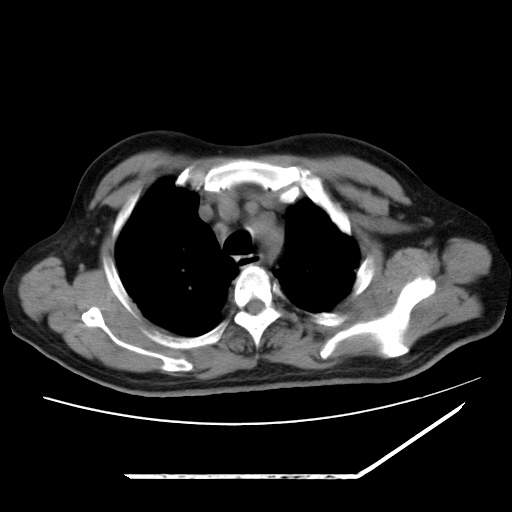

男,57,畏寒,发热

两肺野多发大小不一高密度灶,纵膈内见肿大淋巴结,要考虑转移瘤可能。双侧胸腔少量积液。

双肺多发结节样病灶,部分内见透光区,纵隔内见淋巴结肿大。结核临床如有畏寒,高热,白细胞增高首先考虑迁徙性肺脓肿(多是金黄色葡萄球菌感染)。

1)考虑两肺感染性病变(金黄色葡萄球菌肺炎?);建议抗炎治疗后复查排除其他。2)双侧少量胸腔积液。